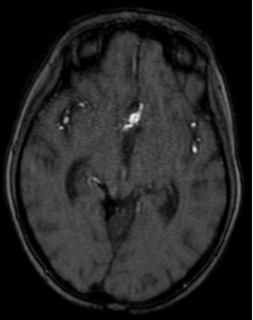

Dos años más tarde, en control por Infectología, refirió cefalea holocraneana pulsátil de moderada intensidad, asociada a mareos, náuseas y vómitos esporádicos. Se solicitó una nueva angioRM, la que arrojó un aneurisma fusiforme de la arteria comunicante anterior con compromiso del segmento A2 izquierdo e irregularidad asociada de M1 derecho (Figuras 3 y 4). Ante estos hallazgos se efectuó angiografía cerebral con colocación de un diversor de flujo, angioplastia con balón y embolización con “coils”.

Figura 3. RM cerebral, secuencia blackblood: dilatación aneurismática de 8.1 x 5.9 mm en el segmento comunicante anterior e irregularidad con reducción de calibre en M1 derecho. La técnica suprime la señal de la sangre en movimiento, haciendo que la luz vascular se observe negra y permitiendo resaltar la pared arterial.